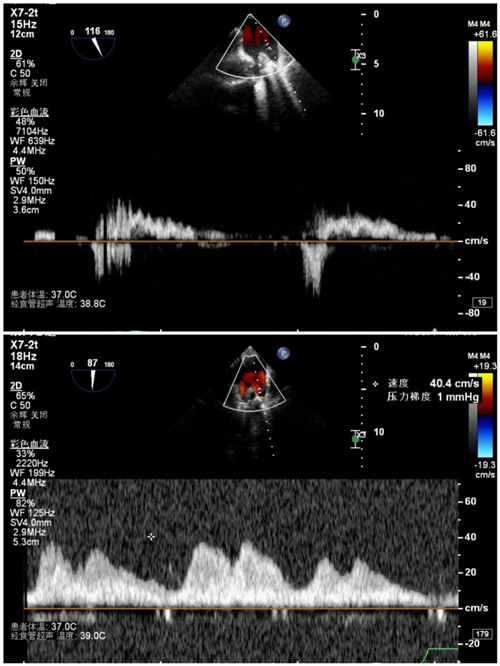

手术前后肺静脉流速

7月9日上午,心内科联合麻醉科、胸外科等多学科,共同为陈奶奶开展手术,术前二尖瓣大量反流,反流程度5+,肺静脉反流明显,术后二尖瓣少量反流,反流程度1+,肺静脉反流消失,手术顺利结束。术后安返病房,次日陈奶奶从不能平卧到能下床活动。在医护人员的精心照顾下,陈奶奶现已顺利出院。